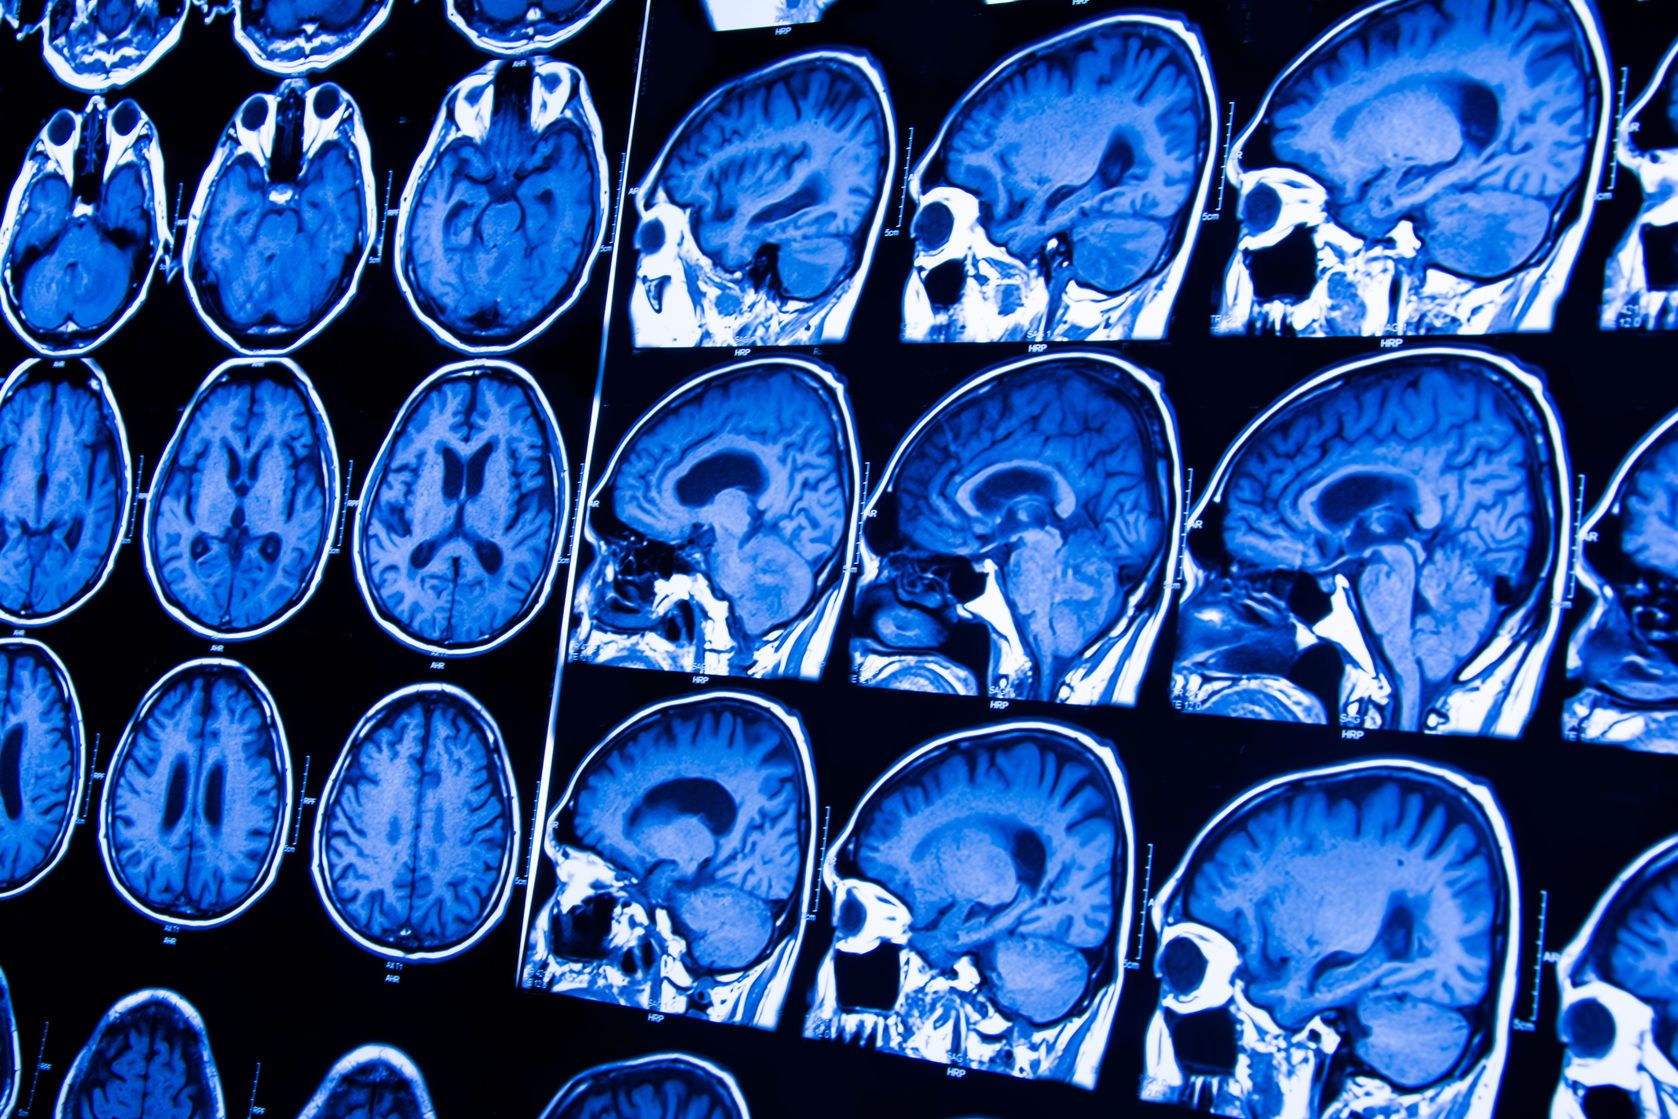

Wylew krwi do mózgu jest stanem, który pojawia się jako zaawansowany skutek chorób układu krążenia takich jak miażdżyca czy nadciśnienie. Dochodzi wówczas do zaburzeń przepływu krwi w obrębie mózgu – głównie zaczopowania naczyń.  Jest to stan bezpośredniego zagrożenia życia dlatego też zauważając objawy, które mogłyby sugerować wylew należy niezwłocznie udać się do szpitala.